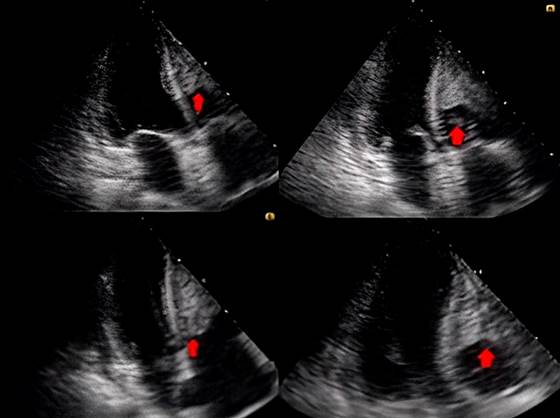

Una TAC de tórax ratificó el proceso consolidativo y derrame pericárdico (grosor: 7 mm), mientras que el ecocardiograma transtorácico evidenció el ventrículo derecho dilatado y la presencia de 2 trombos de igual ecogenicidad, uno que ocupaba la mayor parte de la pared libre y otro redondeado que oscilaba y alcanzaba a protruir la válvula tricúspide (Figura 2), por lo que se inició la anticoagulación con heparina de bajo peso molecular (HBPM: 1 mg/kg/día) y diuréticos.

Figura 2 Ecocardiograma transtorácico que muestra un trombo que cubre la mayor parte de la pared libre del ventrículo derecho con otra imagen de igual ecogenicidad, redondeada, de 1,6 x 1,6 cm, que oscilaba y alcanzaba a protruir por la válvula tricúspide. Cortesía del departamento de radiología del Hospital Regional de la Orinoquia (HORO).